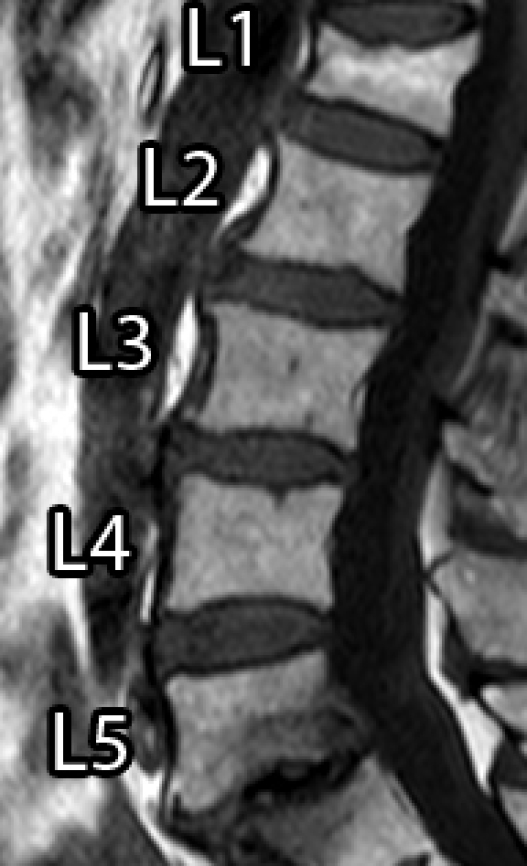

Spinal diseases are quite usual worldwide and can cause significant loss of function and quality of life [1]. A very recurrent disease among older adults is the Vertebral Compression Fracture (VCF), which, in general, is caused by osteoporosis (benign) or bone metastasis (malignant) [2, 3, 4]. In general, VCFs are early detected or diagnosed based on shape or texture using Magnetic Resonance Imaging (MRI) [5, 6, 3, 7]. Usually, a specialist manually segments the Region of Interest (ROI) to aid the diagnose, which can be time consuming and prone to errors, due to inter and intra-subject variability and the subjective judgment that is employed [8].

However, it incorporates expert knowledge gained over several years. Figure 1 shows an example of manual segmentation over five lumbar vertebral bodies (L1-L5).

![]() |

| (a) Original image | (b) Ground-truth |